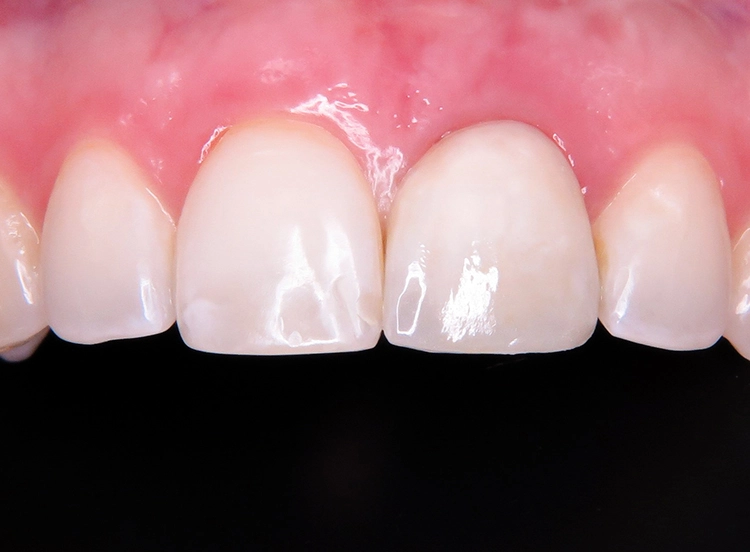

Die junge Patientin konsultierte die Zahnarztpraxis mit Beschwerden am Zahn 21. Der endodontisch vorbehandelte Zahn (multiple Wurzelspitzenresektionen) war mit einer Krone prothetisch versorgt (Abb. 1). Die Krone wirkte im Mund etwas dunkel und hatte einen grauen Schimmer. Da der Zahn zudem immer wieder Beschwerden bereitete, äußerte die Patientin den Wunsch nach einer Neuversorgung. Ansonsten war sie vollbezahnt und funktionell ohne pathologischen Befund. Parodontal zeigte sich eine kleine Rezession im Unterkiefer-Frontzahnbereich.

Zu den schwierigen Anforderungen im Frontzahnbereich gesellten sich hohe ästhetische Ansprüche. Die klinische sowie radiologische Diagnostik (Abb. 2) ergaben, dass der Versuch des Erhalts von Zahn 21 keine sichere Perspektive bot. Die Entscheidung fiel für die Extraktion des Zahnes. Um das Hart- und Weichgewebe bestmöglich vor der physiologischen Remodellierung nach der Extraktion zu bewahren, wurde eine Sofortimplantation geplant.